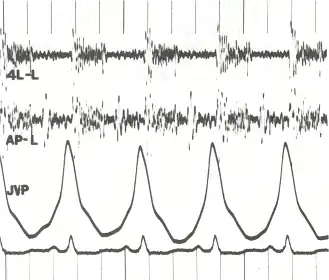

|  Phonocardiogram and jugular venous pulse tracing from a middle-aged man with pulmonary hypertension (pulmonary artery pressure 70 mm Hg) caused by cardiomyopathy. The jugular venous pulse tracing demonstrates a prominent a wave without a c or v wave being observed. The phonocardiograms (fourth left interspace and cardiac apex) show a murmur of tricuspid insufficiency and ventricular and atrial gallops.[1] | |